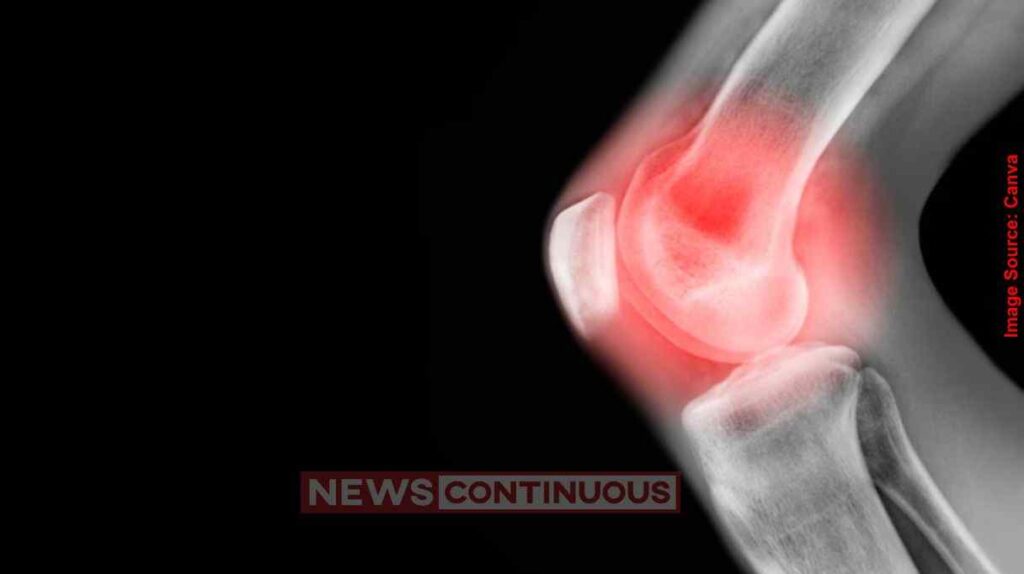

Arthritis Treatment ઓસ્ટિયોઆર્થરાઈટિસ દુનિયાભરમાં લાખો લોકોને પ્રભાવિત કરે છે. હાડકાં વચ્ચે કુશનનું કામ કરતી ગાદી (Cartilage) જ્યારે ઘસાઈ જાય છે, ત્યારે અસહ્ય દુખાવો અને સોજો આવે છે. અત્યાર સુધી પેઈનકિલર અથવા ની-રિપ્લેસમેન્ટ સર્જરી જ તેનો ઉપાય ગણાતી હતી, પરંતુ સ્ટેનફોર્ડ મેડિસિનનો નવો અભ્યાસ આ ક્ષેત્રમાં મોટી ક્રાંતિ લાવવા જઈ રહ્યો છે.

સંશોધકોએ શોધી કાઢ્યું છે કે શરીરમાં રહેલું ’15-PGDH’ નામનું પ્રોટીન ઉંમર વધવાની સાથે કાર્ટિલેજને નુકસાન પહોંચાડે છે. વૈજ્ઞાનિકોએ એક એવું ઈન્જેક્શન (Inhibitor) તૈયાર કર્યું છે જે આ પ્રોટીનની ગતિવિધિને રોકી દે છે. ઉંદર પર કરવામાં આવેલા પ્રયોગમાં જોવા મળ્યું કે આ દવા આપ્યા બાદ ઘૂંટણની ગૂંદી (ગાદી), જે ઉંમરને કારણે પાતળી થઈ ગઈ હતી, તે ફરીથી જાડી અને સ્વસ્થ થવા લાગી.